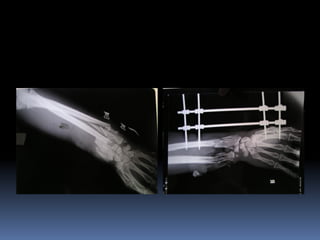

 X quang chi gãy

CẬN LÂM SÀNG: X quang chi gãy  Siêu âm nếu nghi tắc mạch  Công thức máu. Xét nghiệm tiền phẫu  Nếu nặng cần đặt CVP theo dõi  Hình ảnh học các chuyên khoa liên quan như cột sống, bụng, ngực sọ não.